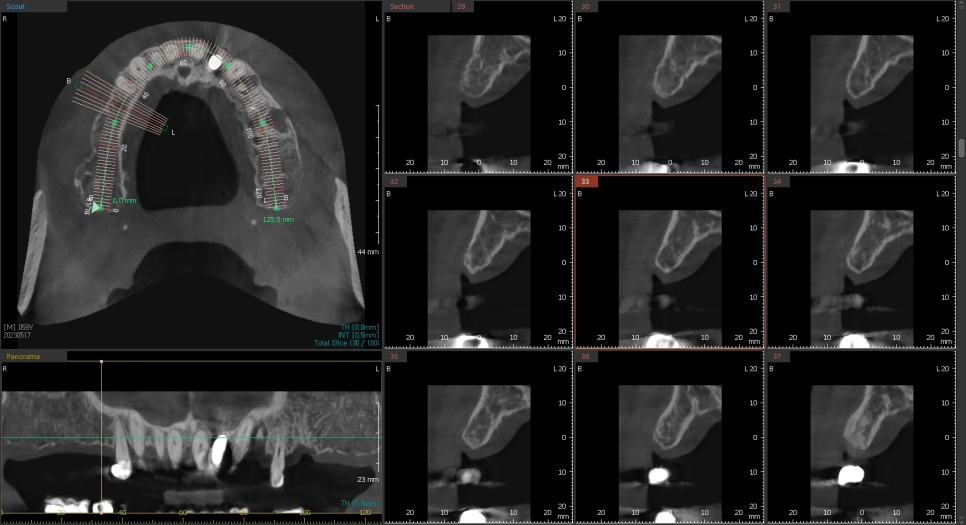

최근 즉시로딩 케이스를 하나 소개드리자면

작은 어금니쪽은 뼈가 살짝 얇지만, 큰 어금니로 갈수록

가용할수있는 잔존골이 많은것을 확인할수 있습니다.

하지만 아래턱에 비해서 골질이 약할수밖에 없는 위턱에 심는 임플란트이고

잔존골의 폭경 또한 만족할만큼 넓진않았기때문에

임플란트 주위로 최소 1mm를 확보하기위해

직경이 얇은 임플란트와와 네비게이션 수술을 선택하였습니다.